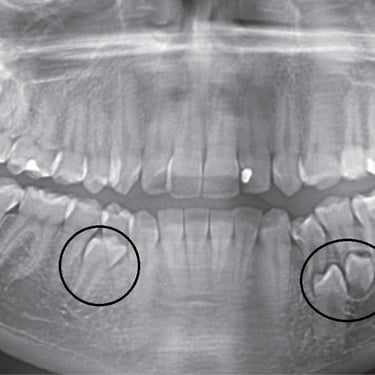

Dientes impactados

Los dientes impactados son dientes que no pueden erupcionar correctamente debido a la falta de espacio o a una obstrucción.

Los pacientes pueden notar que un diente no ha salido, aunque debería haberlo hecho. Esta condición es común con las muelas del juicio y los caninos superiores.

El tratamiento puede incluir la extracción del diente impactado o la creación de espacio para permitir su erupción.